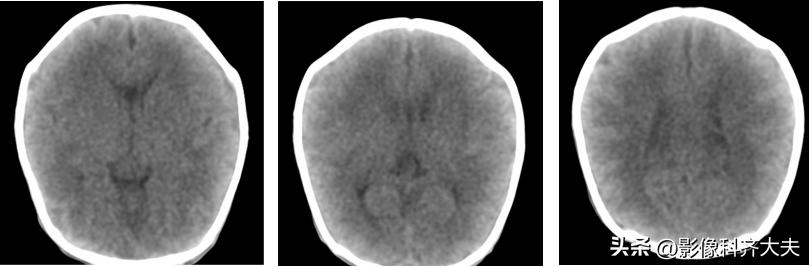

二、早产儿脑白质低密度并非HIE

早产儿脑内含水量高、脑髓质化不全、缺乏髓鞘形成,所以早产儿脑白质低密度是一个正常发育过程,而非脑水肿脑损害表现。